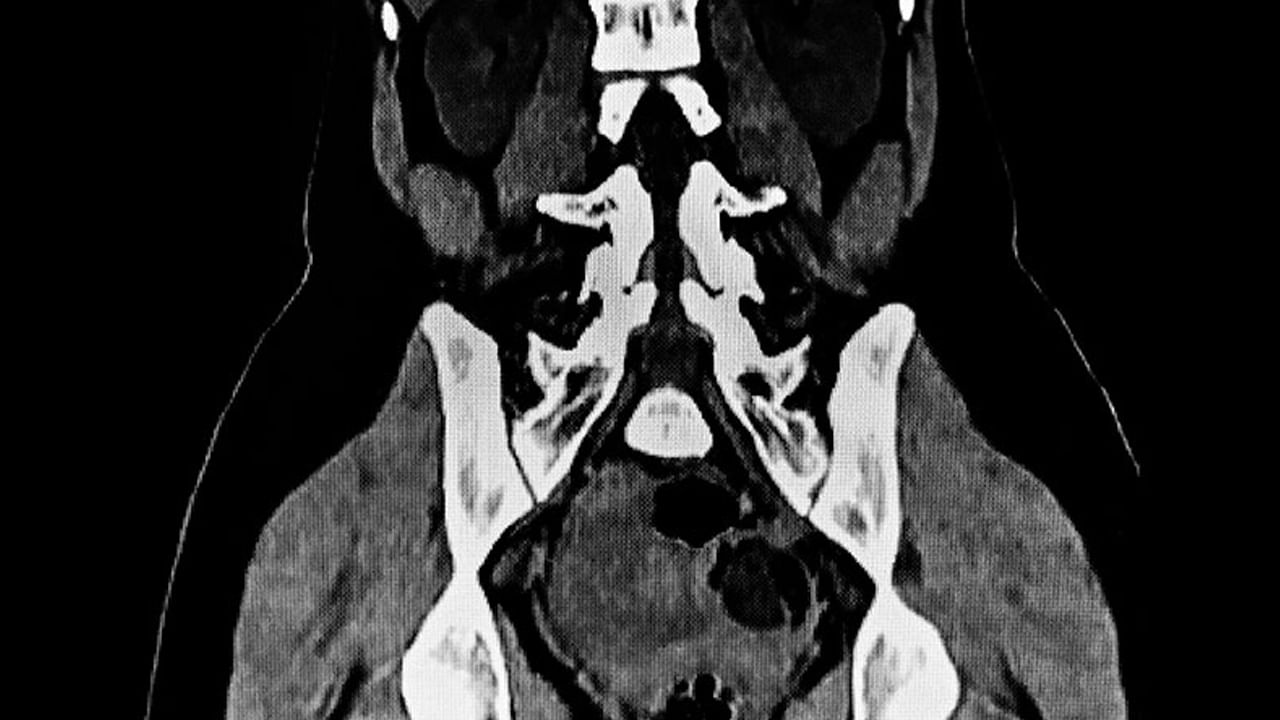

సూర్యాపేట జిల్లా గరిడేపల్లి మండలం తాళ్ల మల్కాపురం గ్రామానికి చెందిన ఓ మహిళ గత కొంత కాలంగా కడుపునొప్పితో బాధపడుతూ హుజూర్ నగర్ పట్టణంలోని సాయిబాబా ధియేటర్ ఎదురుగా ఉన్న విష్ణు జనరల్ ల్యాప్రోస్కోపిక్ ఆస్పత్రికి బుధవారం చికిత్స నిమితం చేరింది. ఆమెకు డాక్టర్ అనంతు విష్ణువర్ధన్ గౌడ్ గురువారం వైద్య పరీక్షలు నిర్వహించి.. స్కానింగ్ చేయగా అండాశయం వద్ద 7 కిలోల కణితి ఉన్నట్లుగా గుర్తించారు. ఈ క్రమంలో సదరు మహిళకు ఆస్పత్రిలో అరుదైన శస్త్ర చికిత్స చేసి అండాశయం వద్ద ఉన్న 7 కిలోల కణితిని తొలగించారు. ప్రస్తుతం ఆమె ఆరోగ్య స్థితి బాగానే ఉన్నట్లుగా డాక్టర్ అనంతు విష్ణువర్ధన్ గౌడ్ తెలిపారు.